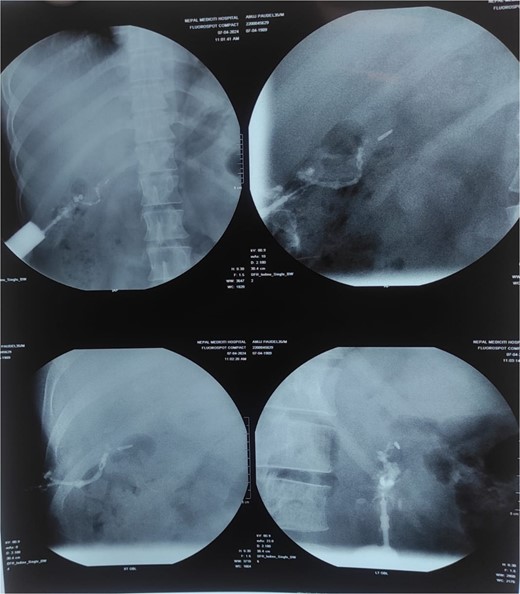

Sinogram showed a blind-ending tube up to the surgical clips in the gallbladder fossa, representing a biliary-cutaneous fistula (Fig. 2).

Sinogram showing blind ending tract extending from sinus opening upto the surgical clips in GB fossa probably biliarycutaneous fistula.